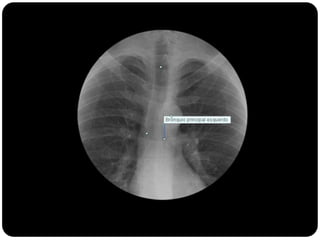

 Brônquios principais originam-se da traquéia

na carina;

 Brônquio direito: ângulo mais obtuso com o

eixo longo da traquéia;

 Direito(2,2cm) mais curto que o

esquerdo(5cm);

Vias aéreas

Traquéia

Brônquios –

PRINCIPAIS

LOBARES

Bronquíolos

Alvéolos

BPD: BLSD

BI - BLM

BI – BLID

BPE: BLSE

BLIE